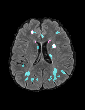

In recent years, data-driven machine learning (ML) methods have revolutionized the computer vision community by providing novel efficient solutions to many unsolved (medical) image analysis problems. However, due to the increasing privacy concerns and data fragmentation on many different sites, existing medical data are not fully utilized, thus limiting the potential of ML. Federated learning (FL) enables multiple parties to collaboratively train a ML model without exchanging local data. However, data heterogeneity (non-IID) among the distributed clients is yet a challenge. To this end, we propose a novel federated method, denoted Federated Disentanglement (FedDis), to disentangle the parameter space into shape and appearance, and only share the shape parameter with the clients. FedDis is based on the assumption that the anatomical structure in brain MRI images is similar across multiple institutions, and sharing the shape knowledge would be beneficial in anomaly detection. In this paper, we leverage healthy brain scans of 623 subjects from multiple sites with real data (OASIS, ADNI) in a privacy-preserving fashion to learn a model of normal anatomy, that allows to segment abnormal structures. We demonstrate a superior performance of FedDis on real pathological databases containing 109 subjects; two publicly available MS Lesions (MSLUB, MSISBI), and an in-house database with MS and Glioblastoma (MSI and GBI). FedDis achieved an average dice performance of 0.38, outperforming the state-of-the-art (SOTA) auto-encoder by 42% and the SOTA federated method by 11%. Further, we illustrate that FedDis learns a shape embedding that is orthogonal to the appearance and consistent under different intensity augmentations.